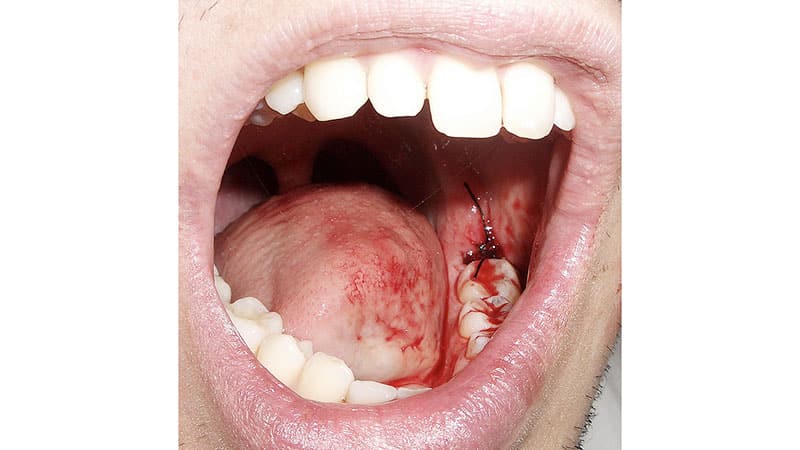

Фото после операции удаления зуба мудрости:

Однако, самое худшее уже позади, так как причиняющий боль зуб, вызывающий воспаление и различные заболевания, был удален. Современные опытные специалисты проводят качественные операции, а современная анестезия позволяет избежать боли.

Тем не менее, после удаления зуба пациенту необходимо следовать определенным рекомендациям, предложенным стоматологом.